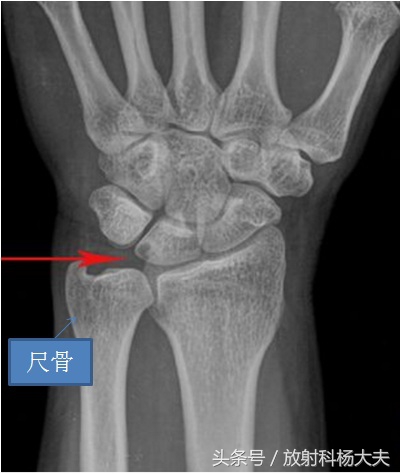

我院骨科医生体格检查发现小爱左腕部受力时腕部尺侧疼痛,腕部活动受限,尺侧张力试验阳性。腕部X光摄片示左侧尺骨远端关节面上移超过桡骨乙状切迹2.4mm,月骨可见囊变。临床症状体征、X线表现结合职业史,临床诊断小爱是尺骨撞击综合征。

(1)腕部外伤史或特殊手部作业史;(2)腕部旋转或尺偏、受力时腕部尺侧疼痛,腕部活动受限,尺侧张力试验阳性;(3)远侧尺挠关节区域有弹响、压疼,特别是尺腕关节间隙的背侧和外侧;(4)腕部X光摄片大多数可见尺骨相对于桡骨长2mm以上(5)腕部MRI检查,多数出现月骨、三角骨的信号改变,部分出现三角纤维软骨信号改变。